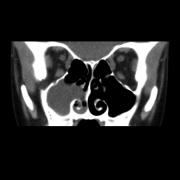

External Approaches to the Paranasal Sinuses

External approaches to the paranasal sinuses have largely been replaced by less invasive endoscopic alternatives in today’s rhinologic practices. However, these approaches each maintain unique advantages in exposure and application over endoscopic approaches. There remain clinical conditions, including extensive frontal disease, bony tumors, trauma and other conditions in which the anatomical access requires more traditional external approaches. The concepts and techniques of these approaches remain paramount components of the competent rhinologist’s skillset.